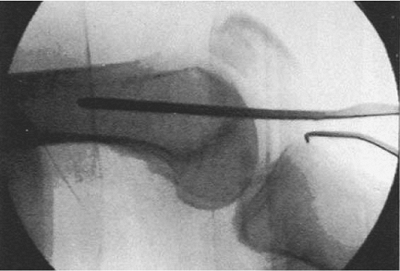

that it is parallel with the trochlear notch in the axial plane (Fig. 45.7)

and parallel with the distal tips of the femoral condyles in the AP

plane. This guide wire is 2 cm proximal to the distal ends of the

condyles and slightly anterior to the midline on the lateral view (Fig. 45.8).